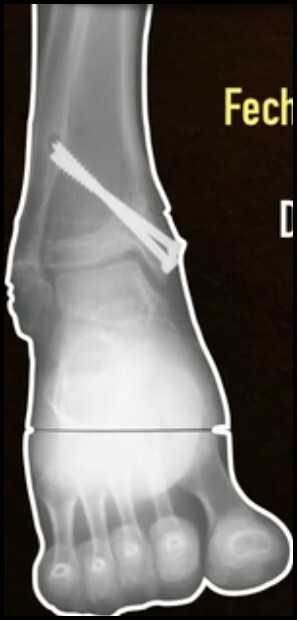

Fechamento da fise de crescimento de posteromedial para anterolateral

13/14 anos até 15-16 anos